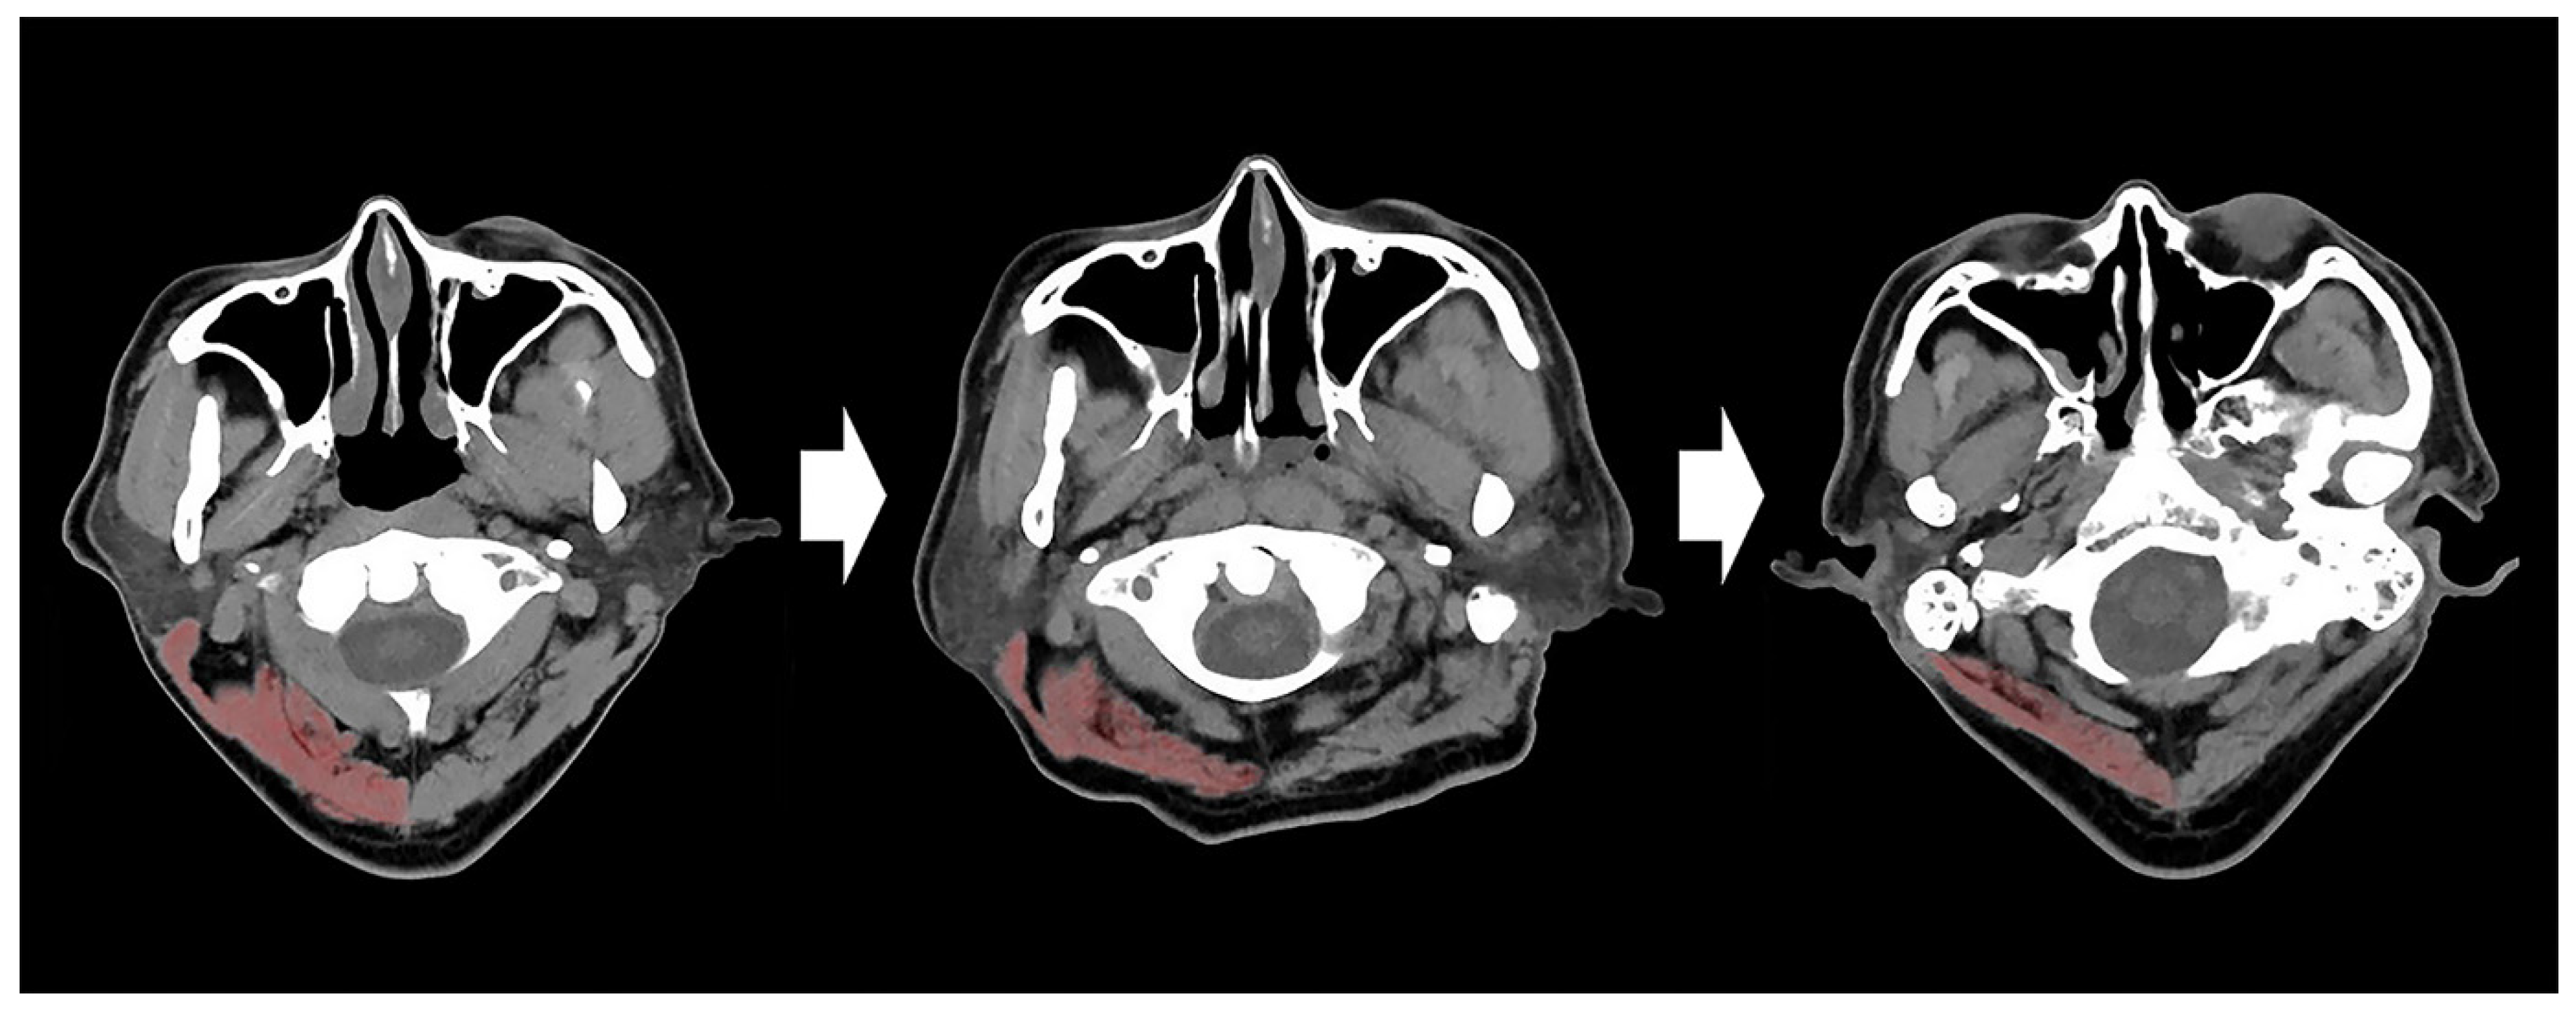

2. Materials and Methods

| CSA | cross-sectional area |

| CT | computed tomography |

| TMT | temporalis muscle thickness |